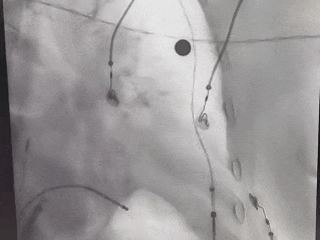

MemoLefort封堵器术中释放后造影评估

封堵器完全释放

肝位造影确认,封堵器位置合适,无残余漏

Lefort封堵器释放

Lefort封堵器评估符合PASS原则,释放封堵器,封堵器位置稳定且未见残余漏,封堵完美。

正足位

肝位

ICE